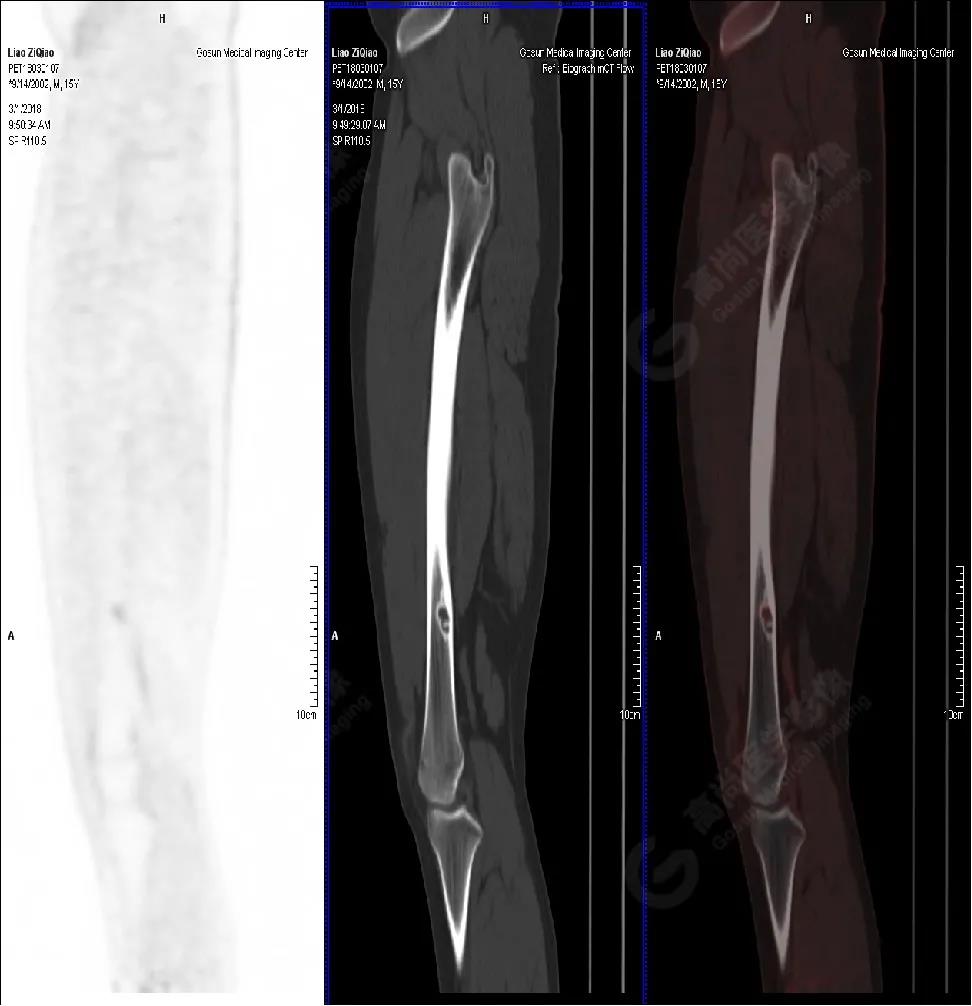

男性,15歲,右側(cè)大腿疼痛1月余,DR提示右側(cè)股骨下段囊性低密度占位。既往無外傷史、否認肝炎、結(jié)核及手術史。

PET/CT檢查

PET/CT表現(xiàn)

右側(cè)股骨下段(內(nèi)側(cè)緣)見骨皮質(zhì)局限性膨脹性破壞,突入髓腔內(nèi),邊界清楚,邊緣硬化,灶內(nèi)見纖維骨嵴,放射性攝取略增高,SUV最大值為1.4,平均值為1.3。

PET/CT診斷

右側(cè)脛骨良性骨病,以非骨化性纖維瘤可能性大。

病理診斷

隨訪結(jié)果:活檢病理確診非骨化性纖維瘤。